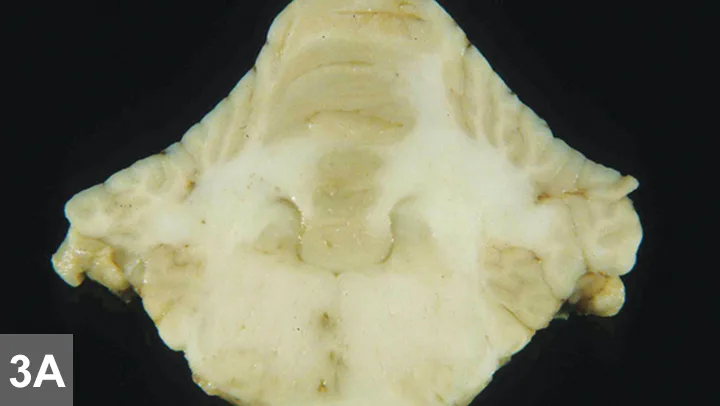

Figure 3A. Pathology samples from another dog with similar histopatho­logic findings: Multifocal areas of malacia (brown–gray spots) in the brainstem (most prominent to the right of midline) and cerebellar white matter are visible on gross pathology samples.

In older patients, thoracic radiography is recommended as a preanesthetic screening tool before MRI to rule out metastatic or primary neoplasia, cardiovascular disease, and pneumonia, which might preclude advanced imaging. MRI and CSF analysis are the hallmarks for diagnosis of intracranial disease. Infectious disease titers are often performed to rule out infectious inflammatory disease. Titers performed should be based on regional exposure risk. Histopathology (Figure 3) remains standard for diagnosing GME and other noninfectious, immune-mediated inflammatory CNS diseases. Stereotactic or surgical biopsy has been described but not commonly performed, and the diagnosis usually remains presumptive.